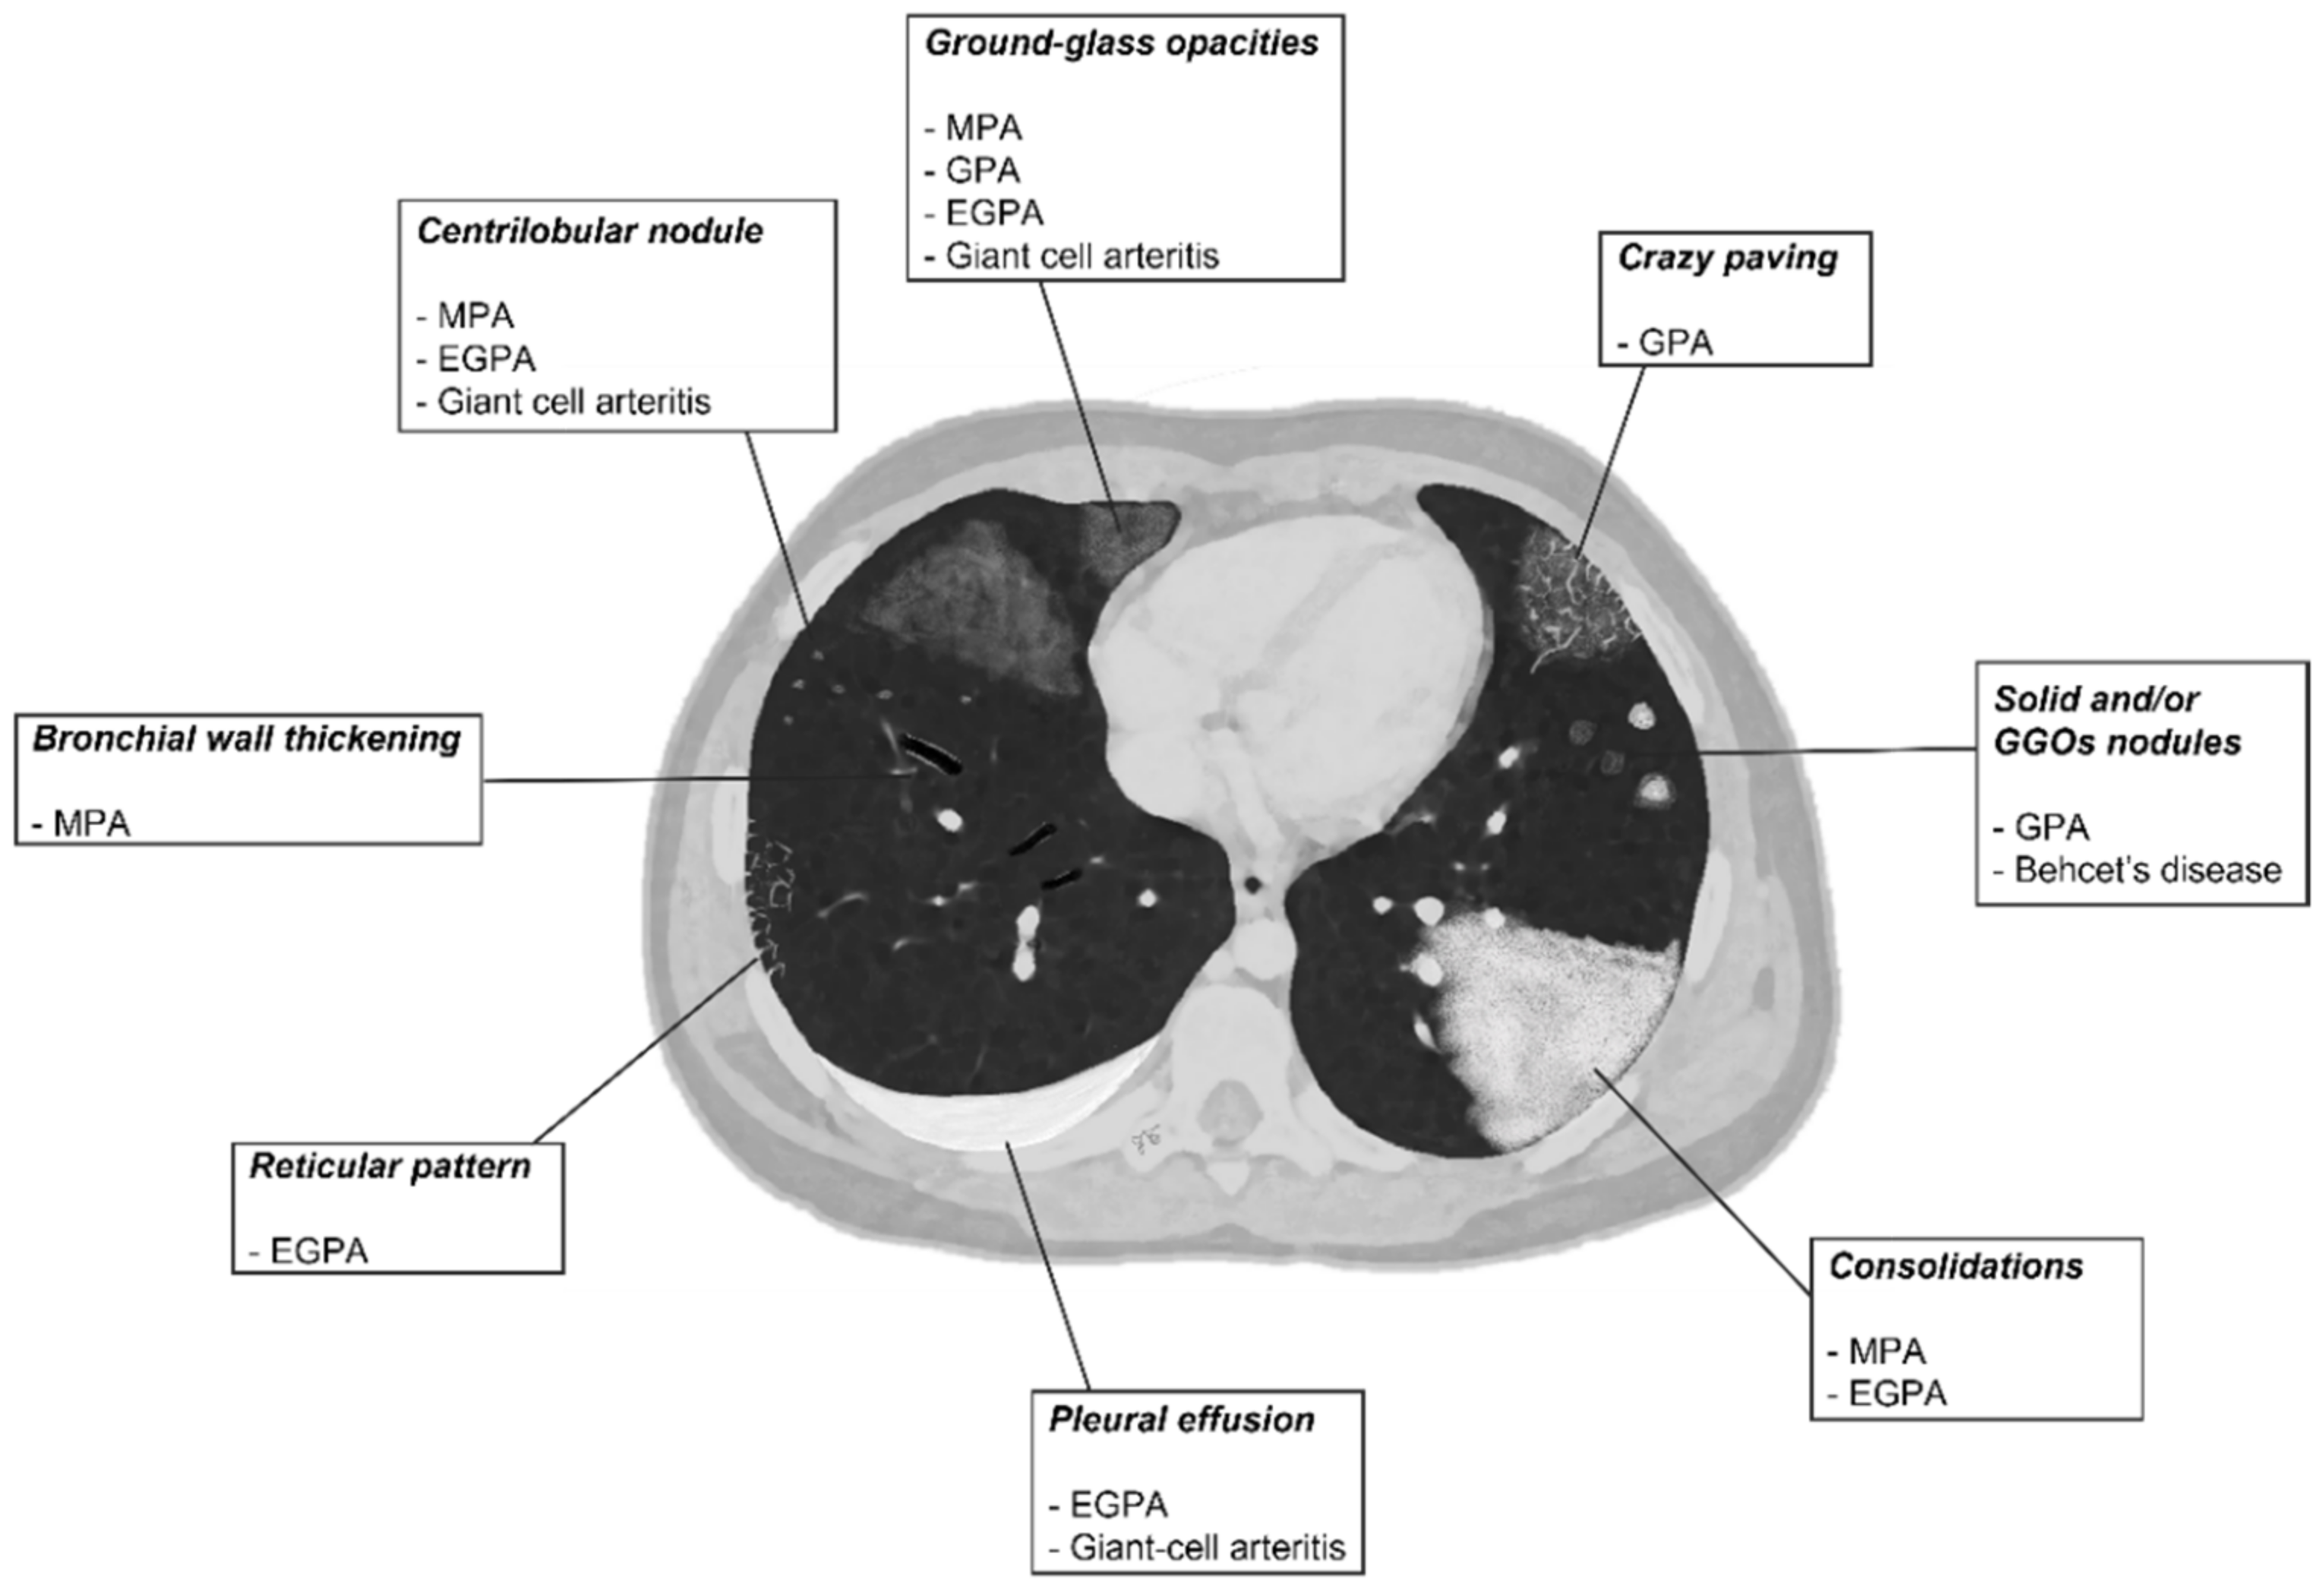

2.3. Microscopic Polyangiitis (MPA)

2.4. Granulomatosis with Polyangiitis (GPA-Wegener’s Disease)

2.5. Eosinophilic Granulomatosis with Polyangiitis (EGPA-Churg-Strauss)

2.7. Giant-Cell Arteritis (GCA-Temporal Arteritis)

2.8. Variable Vessel Vasculitis (VVV)

| Vasculitis | HRCT Features |

|---|---|

| MPA | GGOs due to hemorrhagic alveolitis (common); consolidation, nodules with centrilobular distribution (less common) |

| GPA | Solid nodules, GGOs due to hemorrhagic alveolitis (common); halo sign, crazy paving (less common) |

| EGPA | Migrant GGOs, transient consolidation, irregular bronchial wall thickening, small nodules with peribronchial and centrilobular distribution, pleural effusion. |

| Takayasu arteritis | Stenosis and/or occlusion of segmental arteries; stenosis and/or occlusion of lobular or main pulmonary arteries (less common); C.E. of vessel wall may be evident |

| Giant-cell arteritis | Aneurism or dissection of the thoracic aorta (common); nodules, GGOs, monolateral or bilateral pleural effusion (less common) |

| Bechet’s disease | Subpleural alveolar infiltrates and wedge-shaped or ill-defined rounded areas with increased opacity, pulmonary artery aneurism |